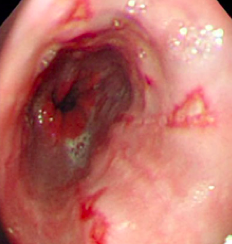

What do you see here?

What histo changes are associated with reflux?